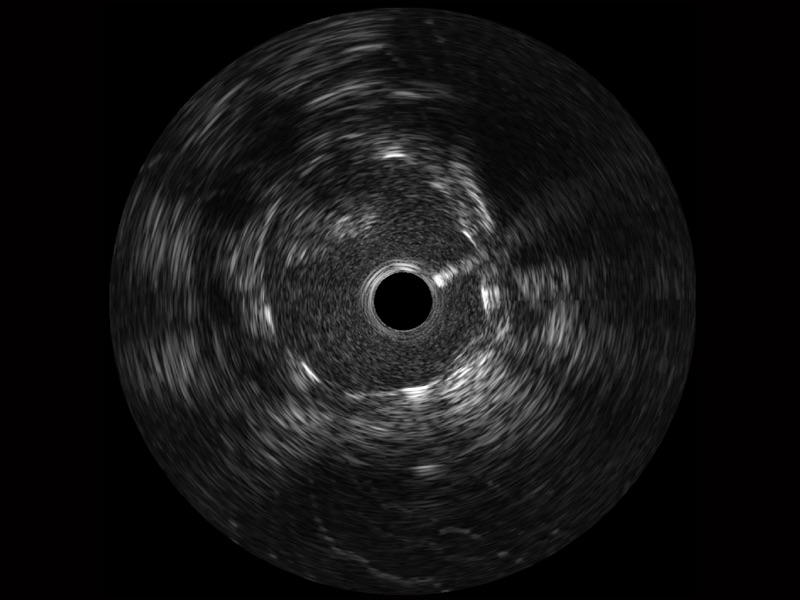

MILE米乐集团官网宽频IVUS图像

对比传统IVUS导管成像,MILE米乐集团官网宽频IVUS图像的近场支架梁显影更细腻,远场中膜外血管仍清晰可辨,兼顾远中近,兼顾分辨力与穿透深度